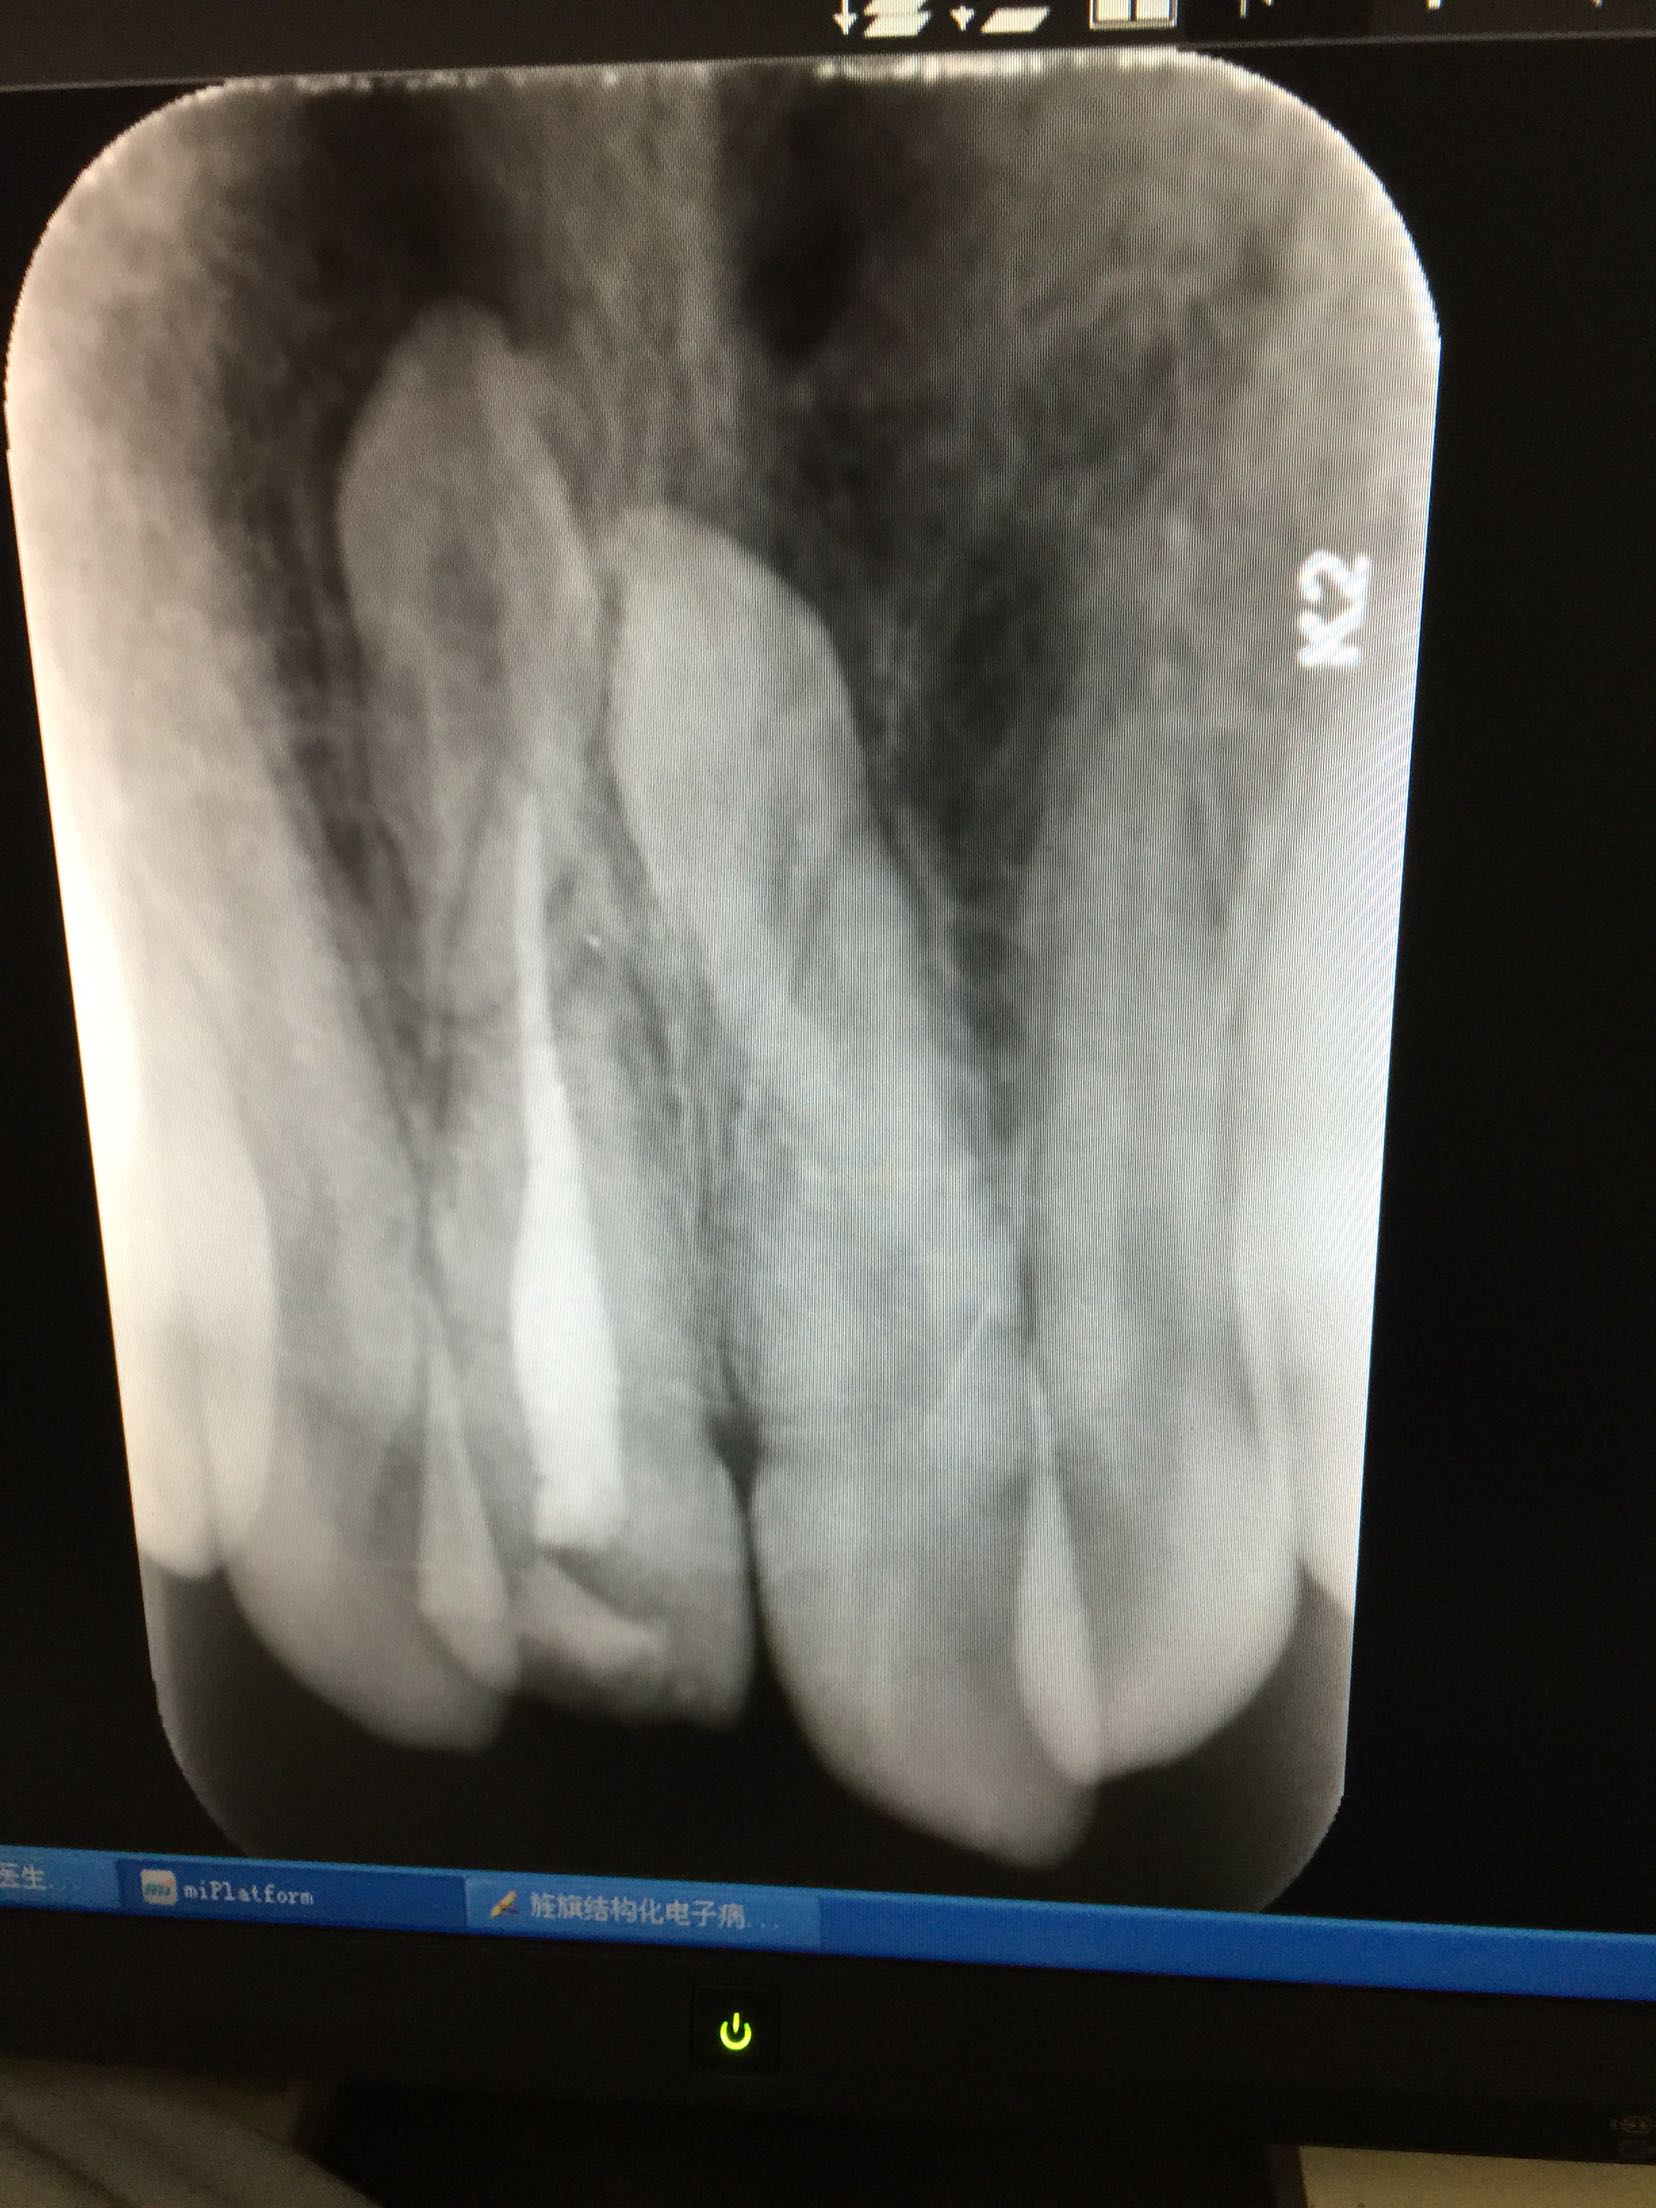

检查:全口卫生好,牙龈正常无退缩。11牙牙冠釉质牙本质折断,累及整个切缘,仅余留颈1/3,断面位于龈上4mm,可见白色暂补料,牙齿颜色正常,叩痛+,冷+,不松,牙髓电活力测试无反应,咬合关系正常。 RVG示:11牙牙冠部分缺损,已累及髓腔,未行根管治疗,很尖区未见异常,11、21牙根尖可见两颗多生牙。